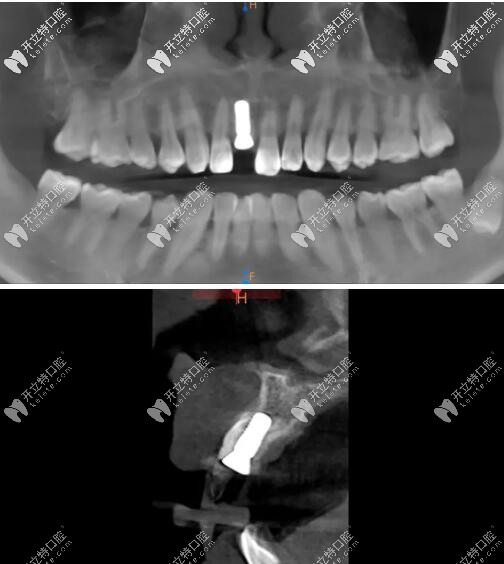

影像學(xué)檢查

門牙磕斷傷及牙根影像學(xué)檢查

被磕的牙冠根向折裂,直達(dá)骨下;

牙根骨量充足;

牙長軸和牙槽骨的方向基本一致。